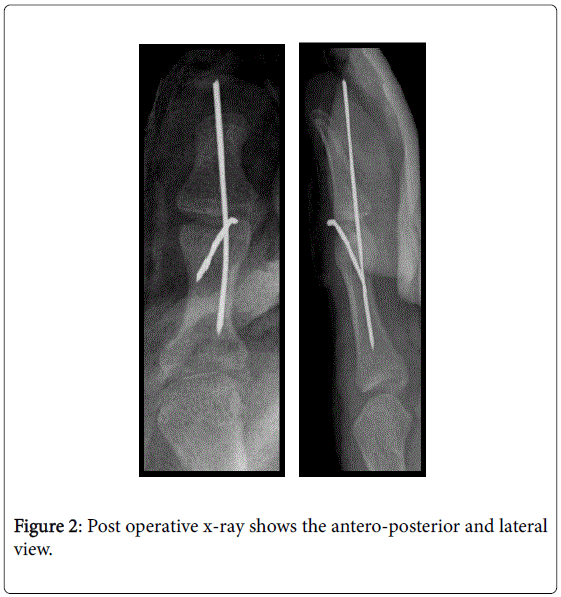

From jocr.co.in

Mallet Finger Fracture Treated with Delta Wiring Technique A Case Mallet Fracture Recovery mallet finger is an injury to the tendon that straightens the tip of your finger or thumb. It happens when an object forces the joint to bend beyond its normal range. mallet finger is an injury to the tendon that straightens the tip of a finger or thumb. learn how to treat and prevent mallet finger, a. Mallet Fracture Recovery.

From www.omicsonline.org

The Ishiguro Technique for the Treatment of Adolescent Mallet Thumb Mallet Fracture Recovery learn how to treat mallet finger with a simple splint and exercises. Diagnosis is made clinically when the distal. It can happen when a hard object hits your fingertip, such. mallet finger is an injury to the tendon that straightens the tip of your finger or thumb. the recovery period for a mallet finger can vary depending. Mallet Fracture Recovery.

The Ishiguro Technique for the Treatment of Adolescent Mallet Thumb Mallet Fracture Recovery learn how to treat mallet finger with a simple splint and exercises. It can happen when a hard object hits your fingertip, such. Here are some essential points. mallet finger is an injury to the tendon that straightens the tip of a finger or thumb. It happens when an object forces the joint to bend beyond its normal. Mallet Fracture Recovery.